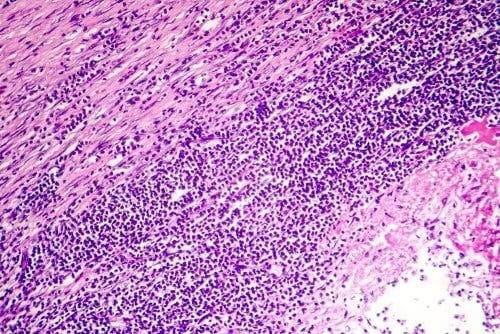

80 %:ssa tapauksia sydänpussitulehduksen syytä on mahdotonta selvittää. Se on kuitenkin hyvin tavallisesti peräisin jonkintyyppisestä infektiosta, hyvin todennäköisesti virusinfektiosta. Joissakin tapauksissa syynä voi olla bakteeri-infektio, mutta vähemmässä määrin, ja vain hyvin harvoissa tapauksissa sydänpussitulehdus voi johtua sieni-infektiosta.

Muissa tapauksissa se on suoraan seurausta sydänkohtauksesta, sydänleikkauksesta tai ruumiinvammasta rintakehän alueella. Toisinaan sydänpussitulehdus saattaa syntyä sydänlihastulehduksen, rintakehän alueen sädehoidon tai tiettyjen lääkkeiden käytön seurauksena.